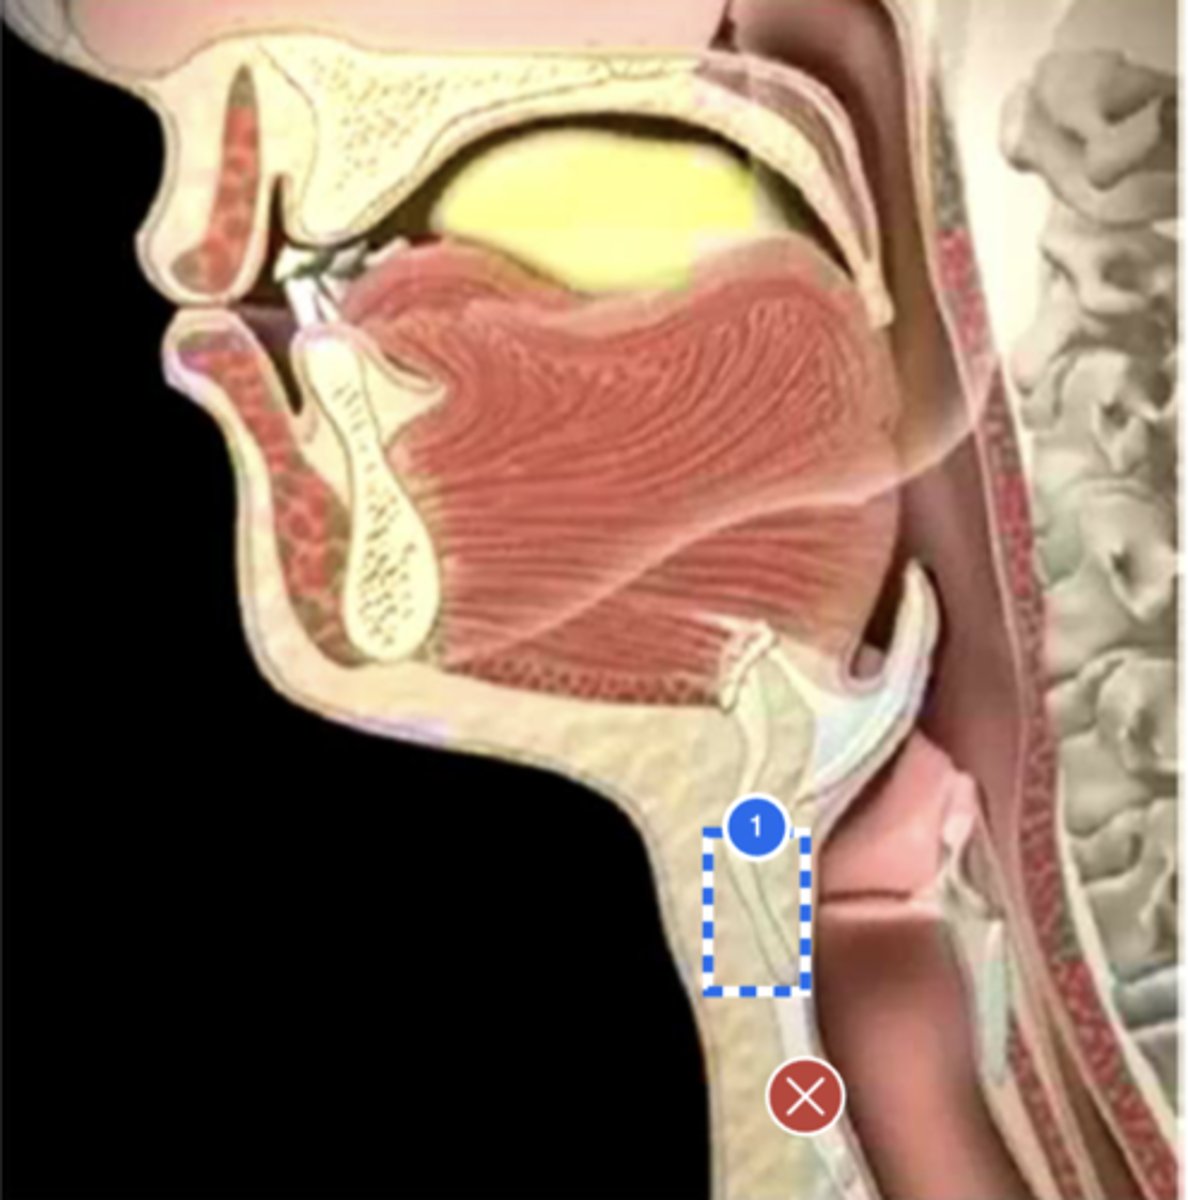

Label base of tongue (lateral view)

label anterior tongue (lateral view)

Label posterior/ back of tongue (lateral view)

Label Mandible (lateral view)

Label velum/ soft palate (lateral view)

Label hyoid bone (lateral view)

Label epiglottis (lateral view)

Label thyroid cartilage (lateral view)

Label posterior cricoid (lateral view)

Label trachea (lateral view)

Label upper esophageal sphincter (lateral view)

Label esophagus (lateral view)

Label posterior pharyngeal wall (lateral view)